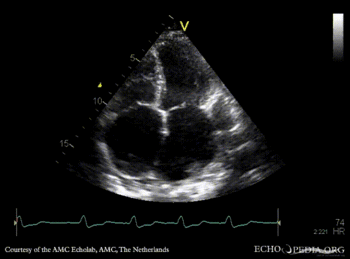

PLAX: dilated coronary sinus A4CH with Color Doppler: severe tricuspid regurgitation